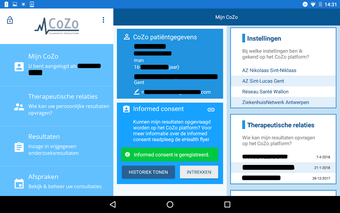

Une application gratuite pour Android, par CoZo Vlaanderen.

CoZo est une application de santé électronique qui permet aux patients et aux médecins de communiquer entre eux et de partager des informations médicales. Elle a été développée pour répondre aux problèmes du système de santé actuel, caractérisé par un manque de communication entre les patients, les médecins et les autres professionnels de la santé.

CoZo permet aux patients de prendre une part active dans leur propre santé et d'être traités comme des participants actifs dans le processus de soins. Les patients peuvent utiliser l'application pour enregistrer leurs données de santé, qu'ils peuvent ensuite partager avec leurs médecins. Les médecins peuvent utiliser l'application pour enregistrer l'historique médical de leurs patients, poser un diagnostic et suggérer un plan de traitement.